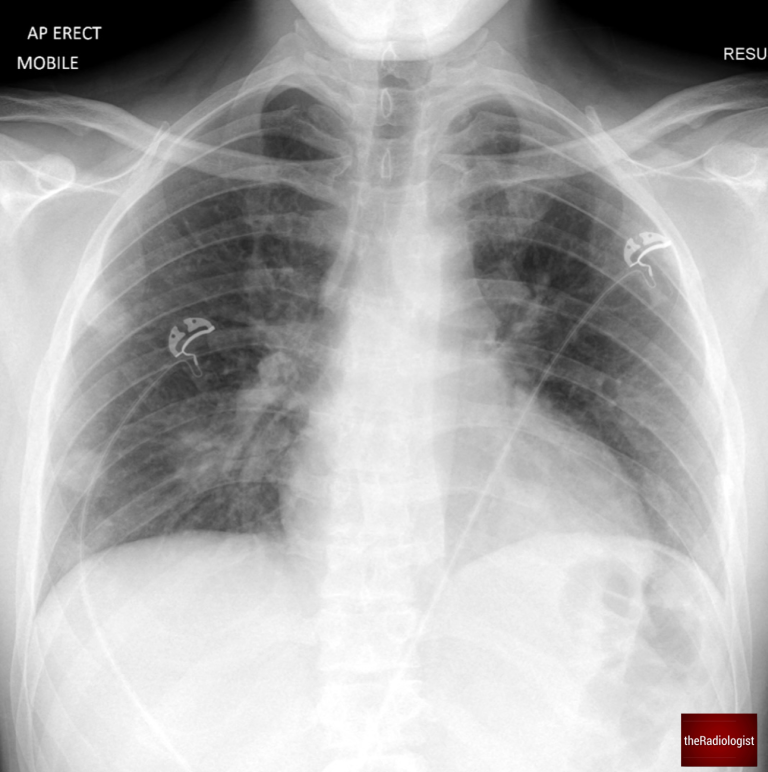

A male in his 20s presents to the emergency department with fever, cough, diarrhoea, and abdominal pain. An anterior-posterior (AP) chest X-ray was performed in ED – we already know by the fact this is AP that the patient is unlikely to be unwell.

AP Chest X-Ray of a male in his 20s